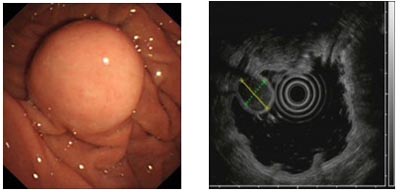

图二  胃间质瘤